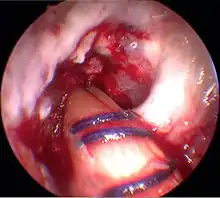

Arthroscopie

L'opération proprement dite commence par l'introduction de l'arthroscope dans le genou du patient. Ceci permet de confirmer définitivement le diagnostic de rupture de LC. Les autres blessures, en particulier celles des ménisques, peuvent être soignées avant la reconstruction du LC.